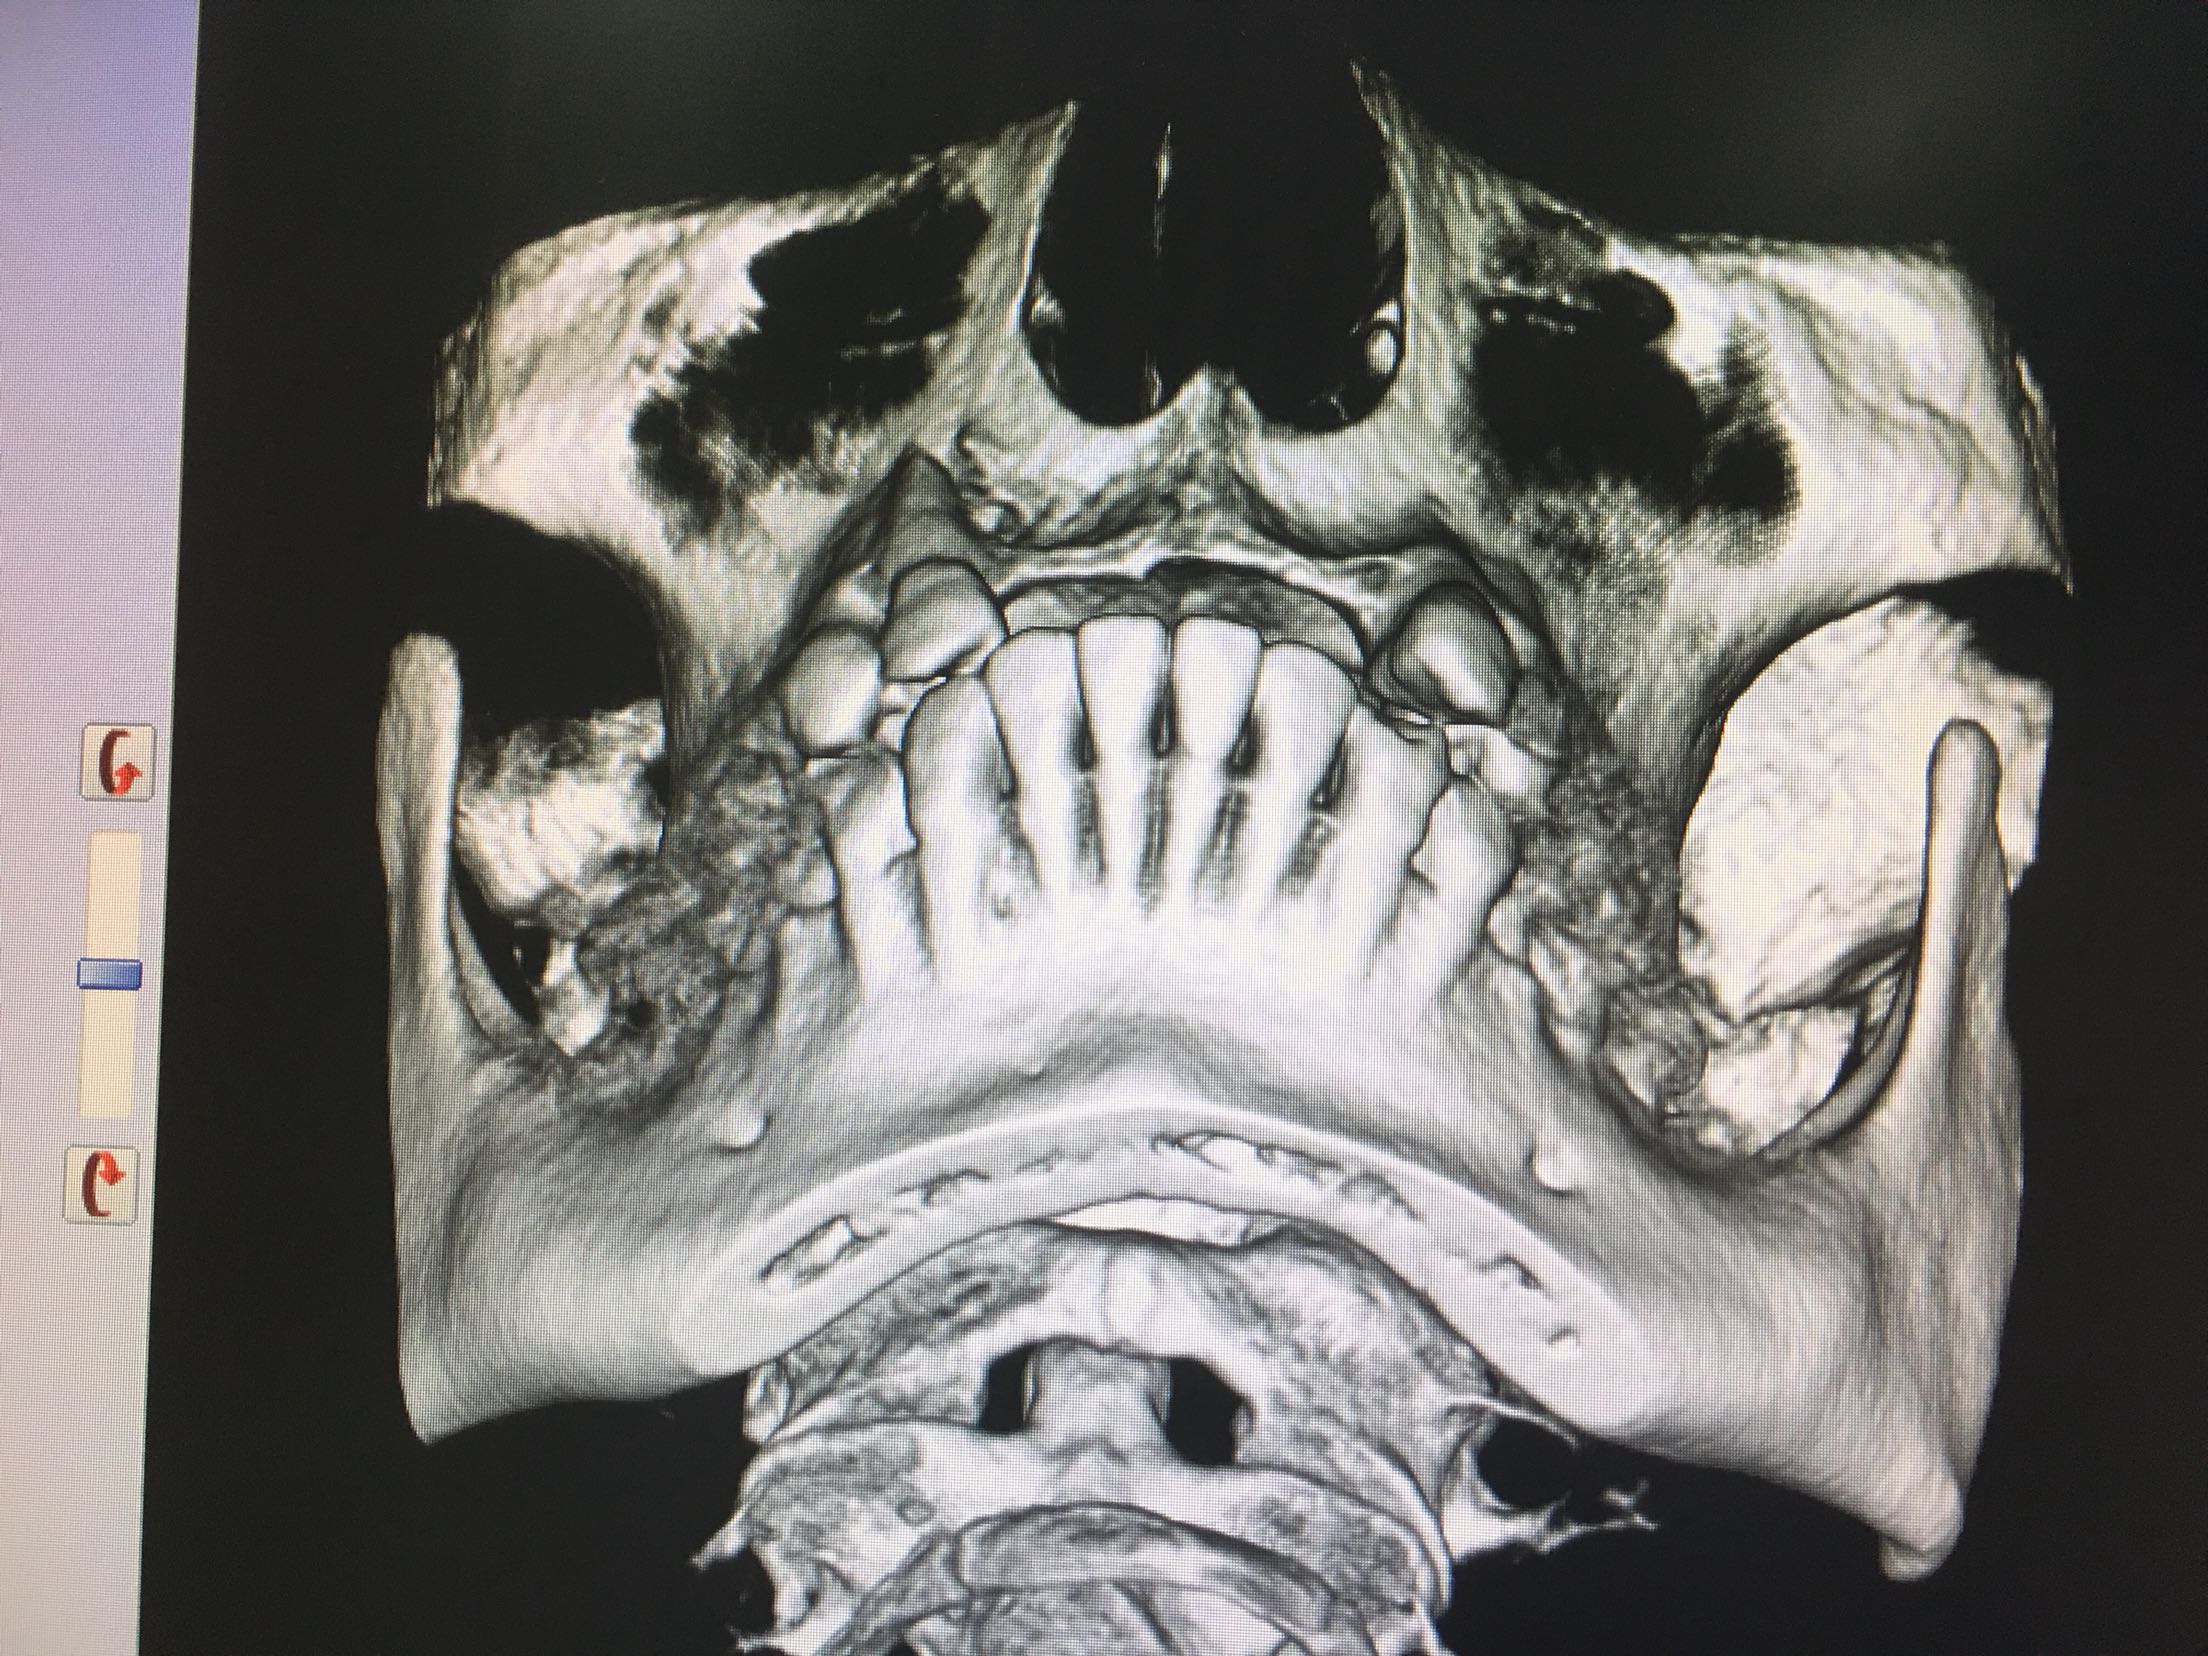

CBCT示11、12、21、22牙缺失,牙槽骨呈刀刃状,38、48牙阻生。

38、48牙超刀拔除,取双侧骨块,11、12、21、22梯形切口切开、翻瓣,切断粘骨膜松弛,骨块钛钉固定唇侧,植入Bio-ss骨粉0.5g,覆盖生物膜,严密缝合!嘱半年后种植!